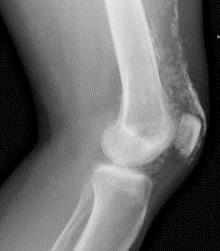

Кальциноз мягких тканей (преимущественно мышц и подкожной жировой клетчатки) является особенностью ювенильного варианта заболевания, наблюдается в 5 раз чаще, чем при ДМ у взрослых [1], и особенно часто в дошкольном возрасте. Кальциноз может быть ограниченный или диффузный, симметричный или асимметричный, представляет собой отложение депозитов солей кальция (гидроксиапатитов) в коже, подкожной клетчатке, мышцах или межмышечных пространствах в виде единичных узелков, крупных опухолевидных образований, поверхностных бляшек. При поверхностном расположении кальцинатов возможна воспалительная реакция окружающих тканей, нагнаивание и отторжение их в виде крошковатых масс. Глубоко расположенные кальцинаты мышц, особенно единичные, можно выявить только при рентгенологическом исследовании.